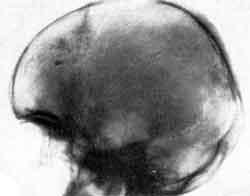

На рентгенограмме черепа: над турецким седлом на границе средней и передней черепных ямок слева определяется конгломерат обызвествленных теней диаметром 1,2 см.

Выше, в передней черепной ямке, в лобном отделе имеются 3 тени овальной формы: 1х0,7; 0,7х0,5; 0,7х 0,3. В заднетеменном отделе слева на уровне затылочного бугра выявился плотный очаг овальной формы 1х0,5 см. На электроэнцефалограмме в 1960 г. обнаружены общемозговые изменения электрической активности головного мозга.

Рентгенограмма черепа и ЭЭГ больного А.

Рентгенограмма черепа больного А. через 4 года после менингита. Обызвествления над турецким седлом. ЭЭГ больного А. через 10 лет после заболевания (объяснение в тексте).